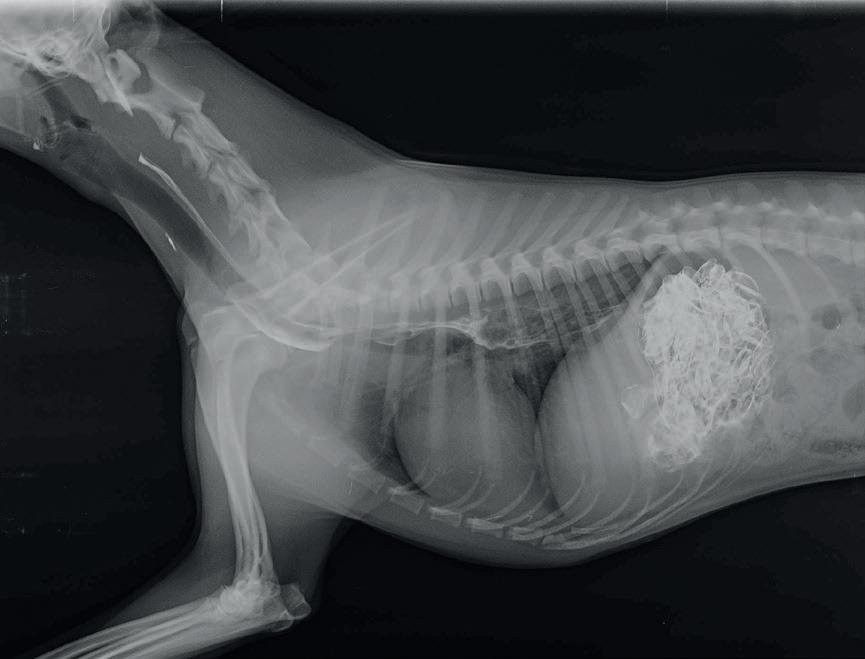

Siendo la regurgitación el principal síntoma, se realizan radiografías de la región cervical, tórax y abdomen craneal y radiografías con contraste del esófagoestomago.

Todas las radiografías de contraste se realizaron mezclando bario en polvo con agua y mezclándolo a su vez con comida húmeda, salvo en la última radiografía que se mezcló con el pienso seco que come actualmente, la comida siempre la ingirió de forma voluntaria. Se realizaron en decúbito lateral derecho y antes de 5 minutos desde la ingesta.

El esofagograma muestra una dilatación esofágica generalizada (fig. 1). El grado de dilatación esofágica se calcula mediante el Diámetro Esofágico Relativo( DER): el diámetro esofágico se mide en su punto más ancho, perpendicularmente al eje longitudinal del esófago a nivel de la superficie intraluminal (DE), relacionándolo en la misma radiografía con la medida de la entrada del tórax (ET): distancia desde el aspecto ventral de la columna vertebral en el punto medio de la primera costilla hasta el aspecto interno del manubrio esternal en el punto del diámetro más estrecho de la entrada del torax. DER=DE/ET

Siendo el DER en la primera radiografía de: 0,92.

En la radiografía del tórax no se observan cambios compatibles con neumonía por aspiración.

1A. Radiografía de contraste mostrando la dilatación esofágica generalizada

1B. Cálculo del DER sobre la figura